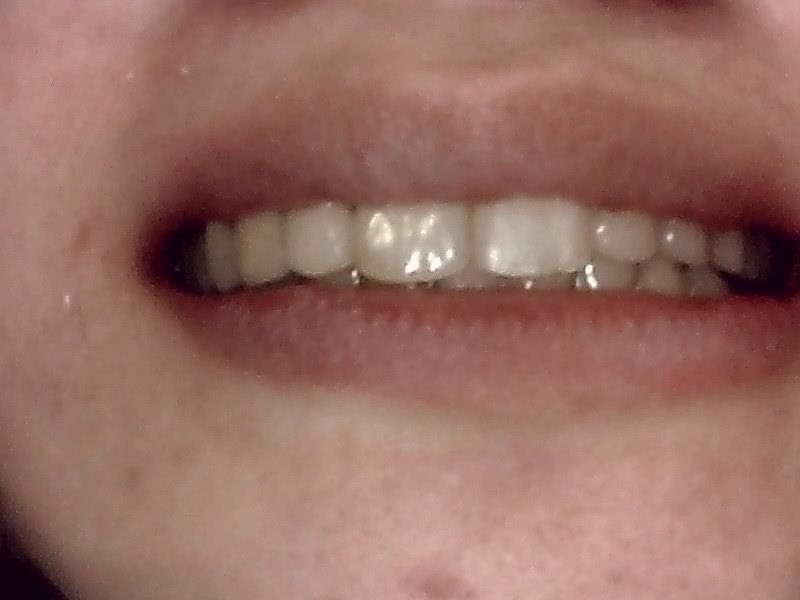

スマイルラインも美しくなり、前突した歯も改善され噛み合わせもしっかり正常に戻しました。

術後の口腔内写真 正面観

術後

術後 リテーナー保定装置で保定します。